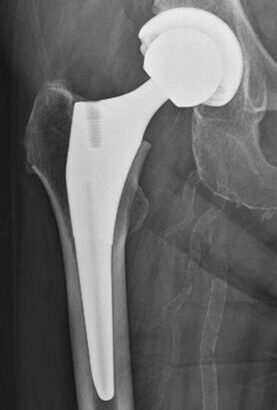

股関節・膝関節の関節軟骨が擦り減り関節の変形をきたす疾患(変形性関節症)や、大腿骨頭への血流がとだえ部分的に骨頭の骨細胞がしんでしまう疾患(大腿骨頭壊死症)は、関節の強い痛みや歩行に大きな支障をきたす原因となります。保存治療で十分な効果が得られない場合、関節をインプラントに置き換える人工関節置換術が痛みを取り除き、歩く力を取り戻すきわめて有効な治療法となります。

当院では、3次元コンピュータ術前計画と連動した最新のロボット支援下手術を行うことで、正確で安全性の高い手術操作やインプラント設置が可能となり、優れた人工関節の耐久性の獲得や脱臼などの合併症防止にも有用です。

人工股関節全置換術(術後)